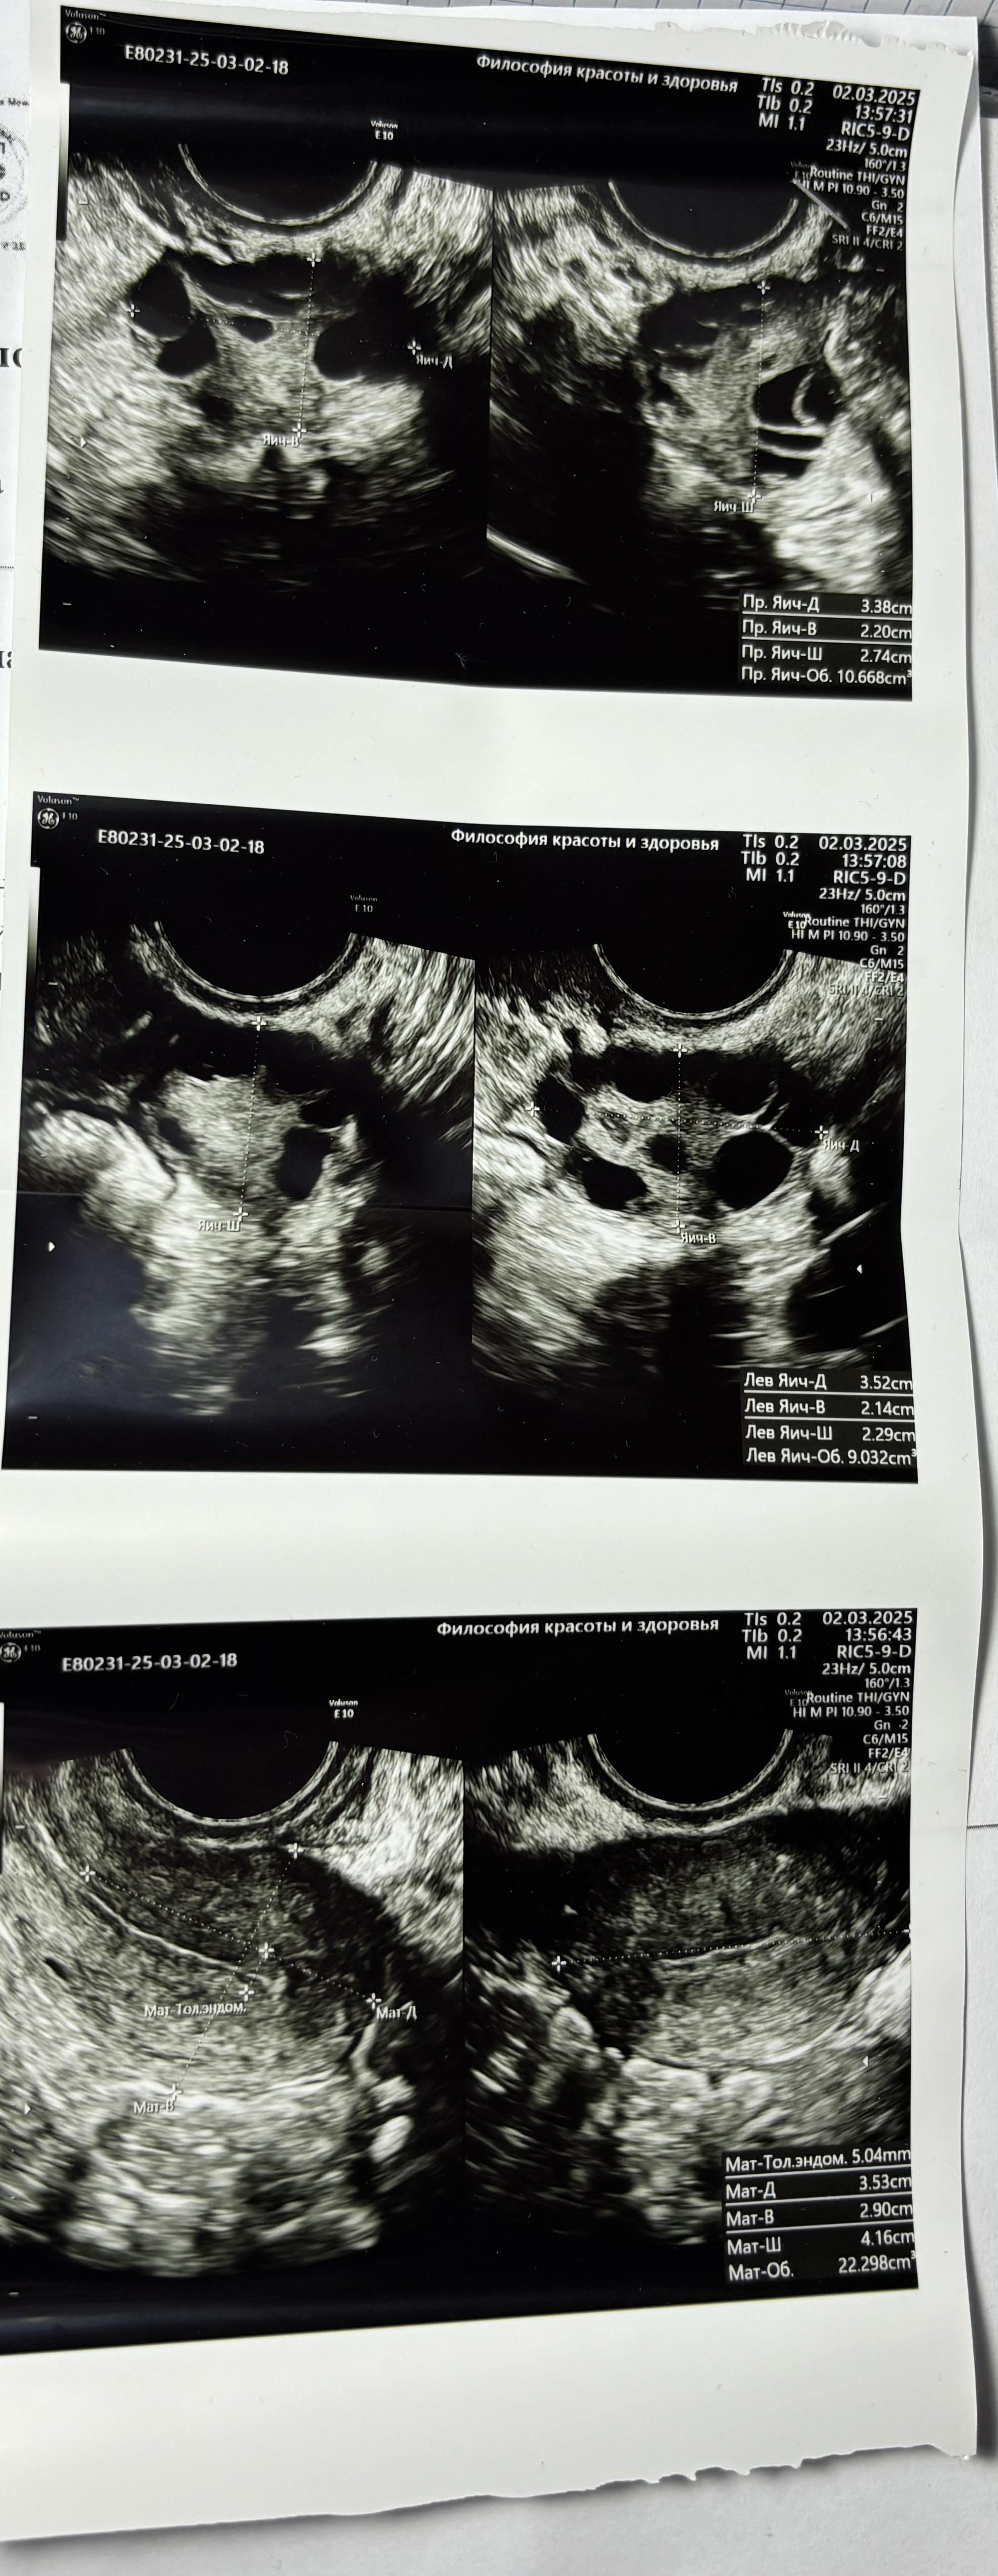

Нина Кривошлыкова, мне сдать ОАК, узи пока что Мужу Мар тест и спермограмму Дальше уже будем отталкиваться от результатов, но узи у меня уже не очень…